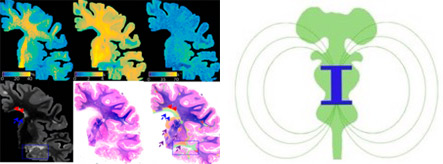

Our work focuses on applying newly developed imaging methods to untangle otherwise hidden disease processes in multiple sclerosis. To achieve our goal, we use high and ultra-high resolution non-conventional imaging techniques both in vivo and post-mortem in humans as well as in animal models of multiple sclerosis. The mission of our lab is that of discovering pathological pathways leading to disease onset and disability progression as to pinpoint targets for new treatments. Major efforts are devoted towards the identification of imaging changes portending neurodegeneration, reflecting microglia activation, or indicating an aberrant immune system. The lab collaborates tightly with the Vanderbilt University Imaging Institute of Imaging Science, VUIIS.